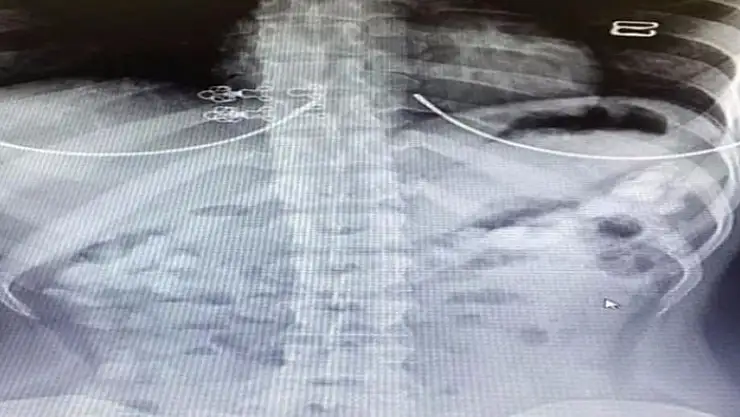

Uyuşturucu maddeleri kapsül halinde yutan 29 yaşındaki Venezüellalı kuryenin iç organlarında çekilen röntgende kokain olduğu görüldü. Maria Rodriguez’in iç organlarında her biri 10-12 gram ağırlığında 78 kapsül ortaya çıktı. Şüpheliden doğal yollarla 71 kapsül çıkarılırken, Rodriguez’in 5 bin Dolar karşılığında kuryelik yaptığı öğrenildi.